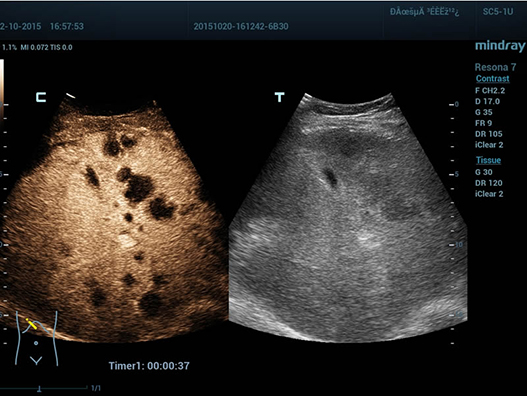

Fin dalla sua fondazione Mindray esplora continuamente nuovi modi per migliorare l'affidabilit├Ā diagnostica. Equipaggiata con la pi├╣ rivoluzionaria tecnologia ZONE Sonography?, la nuova piattaforma ZST+ di Resona 7 porta la qualit├Ā dell'immagine ecografica ad un livello superiore con l'acquisizione per zone e l'elaborazione dei dati canale.